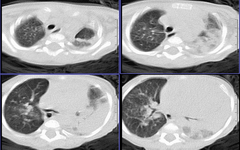

患儿 六月 咳嗽,反复发热二周,加重伴气喘3天

左肺呈大片状实变影,密度欠均匀,边界模糊,残存正常的肺组织呈气肿表现,右肺内可见磨玻璃样改变,如此年幼的婴儿首先考虑左肺发育不良并继发感染可能性大

左肺呈大片状实变影,密度欠均匀,边界模糊,残存正常的肺组织呈气肿表现,右肺内可见磨玻璃样改变,考虑左肺发育不良并继发感染可能性大.图象太小

此患儿于前日死亡,病检结果:

左肺发育不良伴感染.